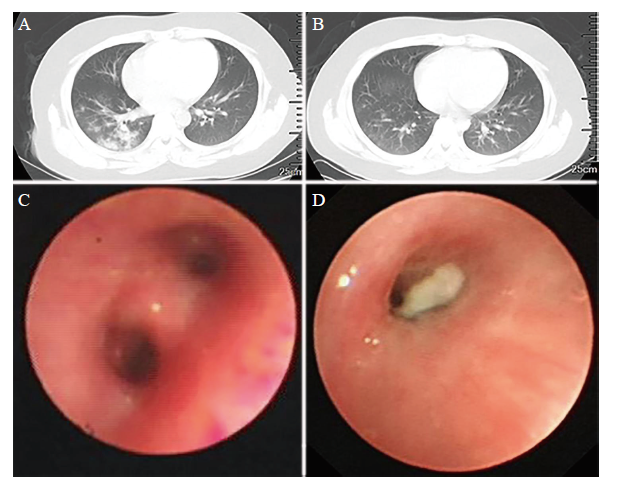

本组58例腺病毒肺炎X线或肺部CT主要表现包括:肺段、一叶或多叶融合病灶29例(50.0%),双肺点片状影21例(36.2%),双肺纹理增多9例(15.5%),纵隔气肿及皮下积气6例(10.3%),节段性肺不张5例(8.6%),见图1A

图1 腺病毒肺炎患儿CT及纤维支气管镜检查图例

A:腺病毒肺炎急性期CT图像;B:腺病毒肺炎治疗1周后恢复期CT图像;C:纤维支气管镜下急性期支气管黏膜炎症改变;D:纤维支气管镜下可见条索状塑型支气管黏液栓

本组58例中20例行纤维支气管镜检查,均表现为病变处支气管内膜炎,14例(70.0%)表现为急性炎症改变,支气管黏膜充血、肿胀、可吸出少量黏稠分泌物,见图1C;4例(20.0%)表现为慢性内膜炎改变,黏膜表现为肿胀、苍白;4例(20.0%)合并有气道先天性发育异常(3例支气管狭窄,1例支气管软化);1例(5.0%)支气管部分黏膜剥脱、糜烂、少量出血,存在黄白色黏液栓堵塞,可以吸出条索状塑型支气管物,见图1D

五、治疗及转归

有研究提示,腺病毒肺炎患儿肺部啰音出现时间晚,而影像学改变较肺部体征出现早,腺病毒肺炎早期表现为肺段及大叶实质浸润、明显肺气肿、间质性肺炎改变或合并大量胸腔积液时,应警惕重症腺病毒肺炎[11,12]。所以,影像学检查对于腺病毒肺炎的诊断具有重大意义。近年来,纤维支气管镜技术被广泛应用于腺病毒肺炎的诊断,在纤维支气管镜下可以直视病灶,直观明确病变性质和炎症程度,为治疗方案提供指导,同时,通过纤维支气管镜对肺叶或肺段进行充分灌洗,可起到药物难以达到的作用,从而改善治疗效果[13]。本组病例中有20例进行了纤维支气管镜检查,采用纤维支气管镜清除气管内痰栓能取得较好的疗效,同时可以早期发现先天性气道发育异常。